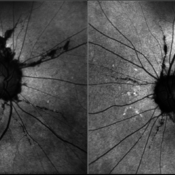

Juvenile X-linked Retinoschisis

Nov 8 2022 by Vaidehi Sathaye

Retro image of RE of a 9 year male patient with Juvenile X-linked Retinoschisis

Photographer: Dr. Vaidehi Sathaye

Imaging device: Mirante

Condition/keywords: foveal schisis, retro mode